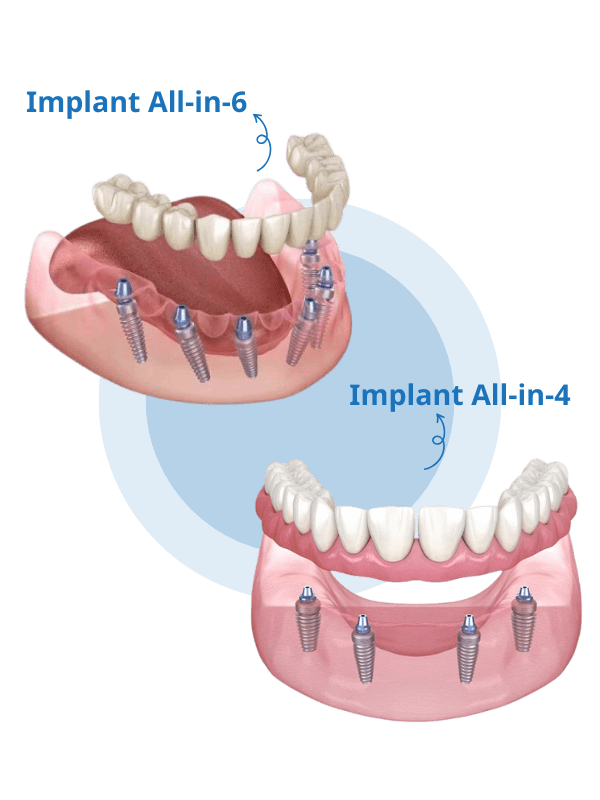

Trồng răng Implant toàn hàm All-on-X là phương pháp cấy từ 4-6 trụ Implant vào hướng thuận lợi của xương hàm để làm trụ vững chắc, giúp nâng đỡ phục hình cho 12-14 răng bên trên. Qua đó giúp phục hình hàm răng cho bệnh nhân mất nhiều răng, sắp mất toàn bộ hay mất răng toàn hàm (chủ yếu xảy ra ở giai đoạn trung niên hoặc người cao tuổi).

Hiện nay, có 2 phương án cấy ghép Implant toàn hàm phổ biến là All-On-4 và All-On-6.

Trồng răng Implant toàn hàm All-On-4

Là giải pháp cắm 4 trụ Implant trên 1 hàm, thường áp dụng trong trường hợp mất răng hàm dưới. Trong đó, 2 trụ giữa đặt ở vị trí răng trước và 2 trụ hai bên đặt vào vị trí răng sau (răng hàm).

Trồng răng Implant toàn hàm All-On-6

Giải pháp cắm 6 trụ Implant trên hàm phù hợp cho người có xương hàm quá yếu. Bác sĩ sẽ cắm 4 trụ giữa đặt ở vị trí răng trước và 2 trụ hai bên được đặt ở vị trí răng sau (răng hàm) giúp nâng đỡ răng vững chắc hơn.